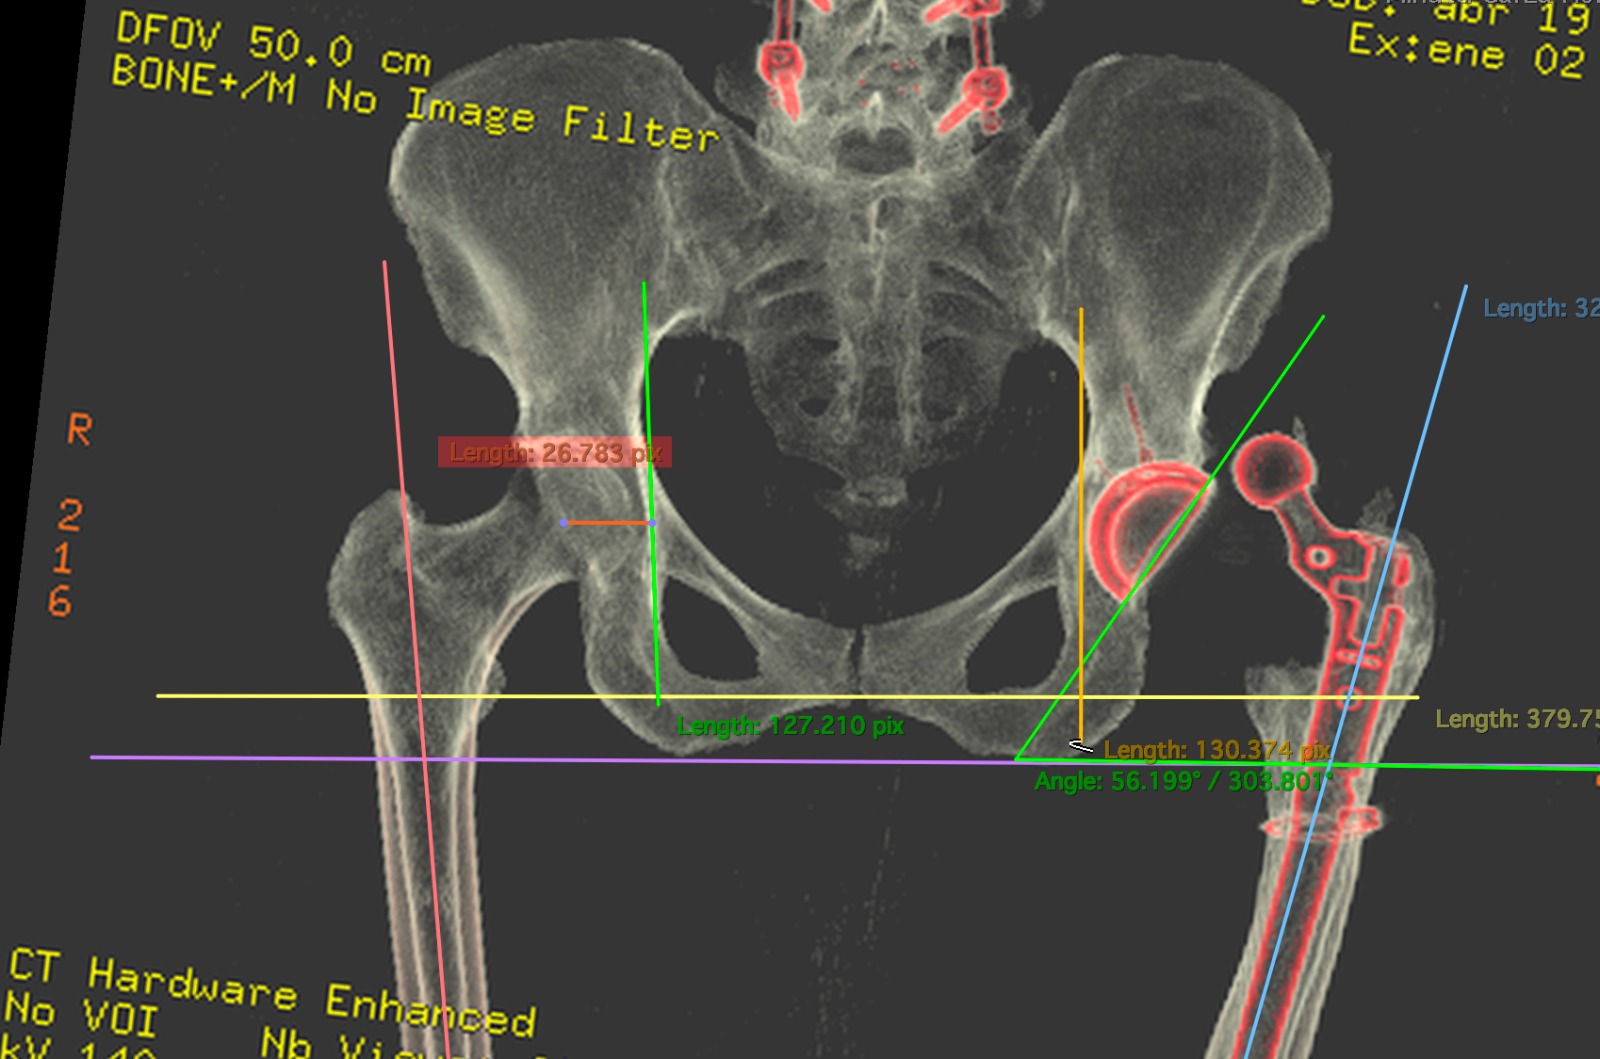

Prótesis de Rodilla

Prótesis de Cadera

Cirugía para reemplazar una cadera desgastada y recuperar la movilidad.

Galería

Conoce al Dr. Camarillo

Imágenes y videos del doctor y sus instalaciones en Monterrey.

- Revisión de estudios de imagen (RX, RM)